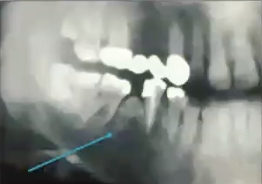

Pano of osteoma

Well circumscribed radiopaque lesion

Radiographic image of osteoma